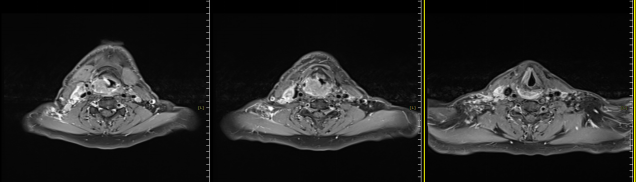

The patient was admitted to our hospital on January 7, 2025, and underwent multidisciplinary consultation before receiving carbon ion therapy for hypopharyngeal malignant tumor on January 16, 2025. The prescribed doses were as follows: PTVp: 68Gy (RBE) / 17Fx, PTVnd-L: D95% = 64Gy (RBE) / 16Fx, PTVR: 60Gy / 15Fx, PTVL: 56Gy (RBE) / 14Fx. Concurrently, cisplatin monotherapy combined with nimotuzumab injection for targeted therapy was administered. A follow-up neck MRI showed a reduction in the primary lesion and bilateral neck lymph nodes compared to pre-treatment, with a recent evaluation indicating a partial response (PR).

MRI before carbon ion therapy